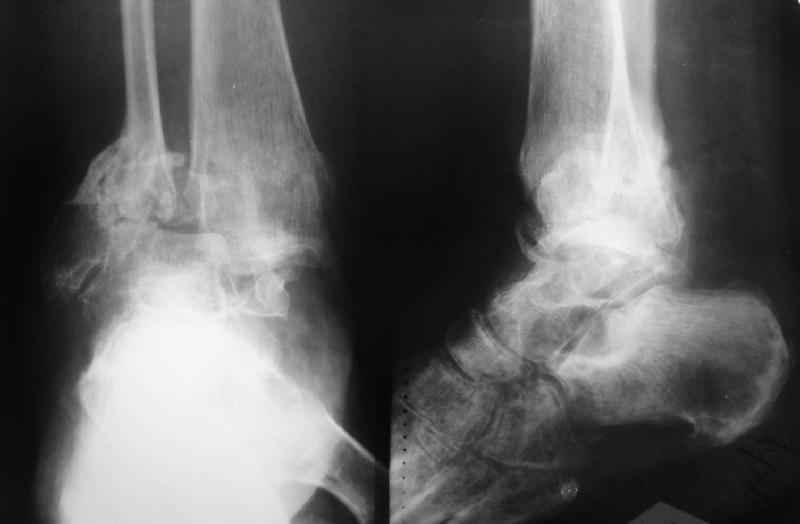

Пациентка 56лет поступила через 5,5 мес. после открытого 2-х лодыжечного перелома,

наружного вывиха правой стопы, осложнённого гнойным артритом.

через 3 недели после травмы в ОКБ выполнена артротомия, некрсеквестрэктомия б/берцовой

кости, ещё через неделю - аутодермопластика по Тиршу. К нам больная поступила через 5,5 мес.

Выполнен ЧКО, остеотомия м/берцовой кости, аппаратное вправление вывиха. Планируется

артродез голеностопного сустава. По медиальной поверхности голени на месте

аутодермопластики сформировался грубый рубец, спаянный с б/берцовой костью. Больная

ходит на костылях с частичной опорой на правую стопу. ВОПРОС: 1) возможно ли в данной ситуации

обойтись компрессионным артродезом в АВФ? 2) какой вид кожной пластики и в какие сроки

целесообразен?